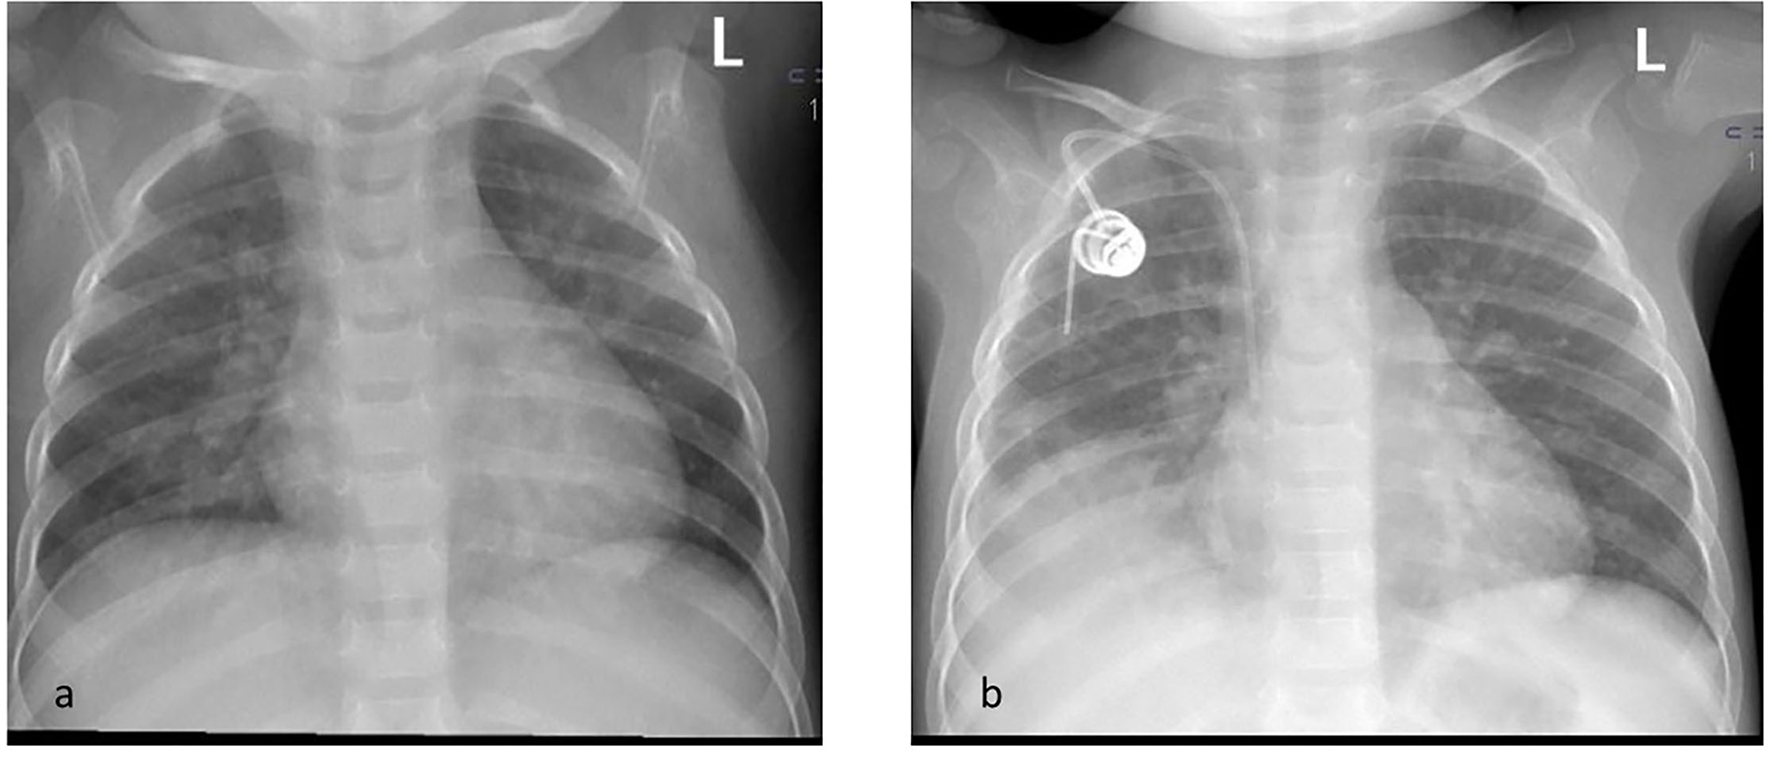

Physical examination on admission showed no abnormalities. Palpation and ultrasonography did not reveal hepatosplenomegaly. Chest X-ray showed peribronchial cuffing (Figure 1).

Figure 1

Chest x ray on the day of admission (a) showing peribronchial cuffing and after 3 monthes (b) with consolidation of right mid and lower zones.

The clinical picture of pulmonary mucormycosis can vary depending on the immune status of the patient. Symptoms include fever, cough, chest pain and dyspnea (17). On imaging studies, pulmonary mucormycosis does not produce specific findings. It may manifest as a single nodule, lobular consolidation as in pneumonia, cavitary lesion or disseminated appearance (18). The clinical and radiological manifestations of pulmonary mucormycosis were not confirmed in our patient.